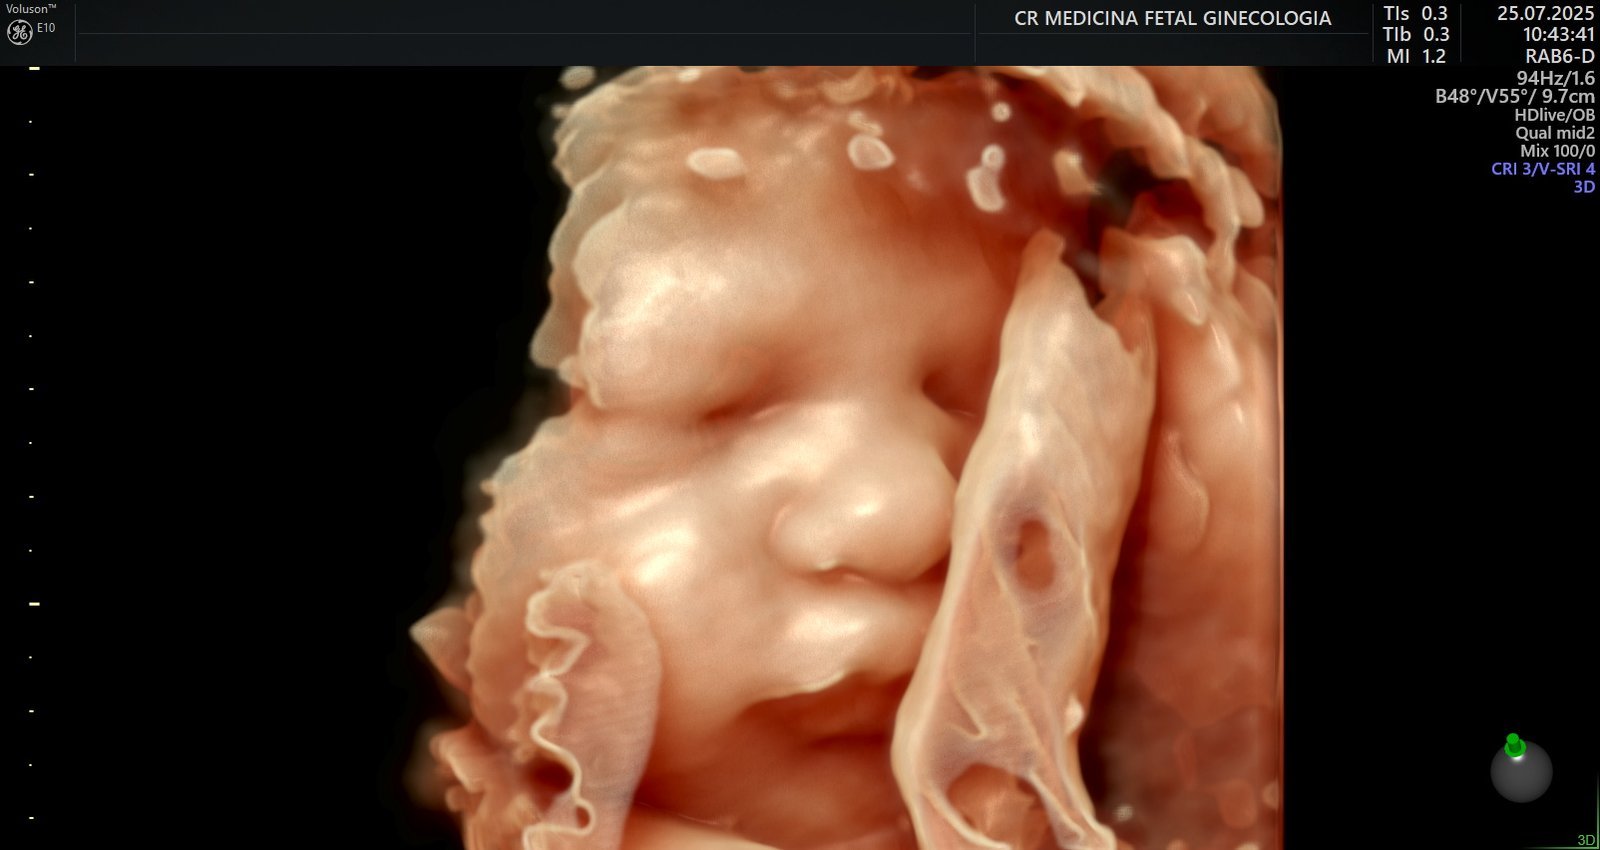

Ultrassonografia 3D e 4D: Permite visualizar o bebê em alta definição, em tempo real, em qualquer idade gestacional, proporcionando um vínculo ainda maior entre a família e o bebê.

• Tecnologia avançada em ultrassonografia 2D, 3D e 4D, com aparelho de ultrassonografia de ponta – Voluson E10